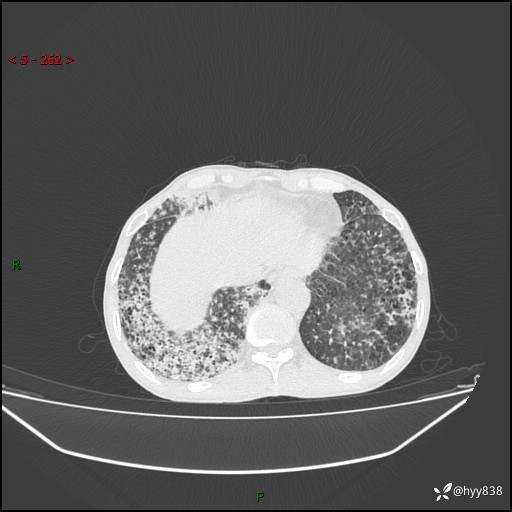

胸部CT平扫